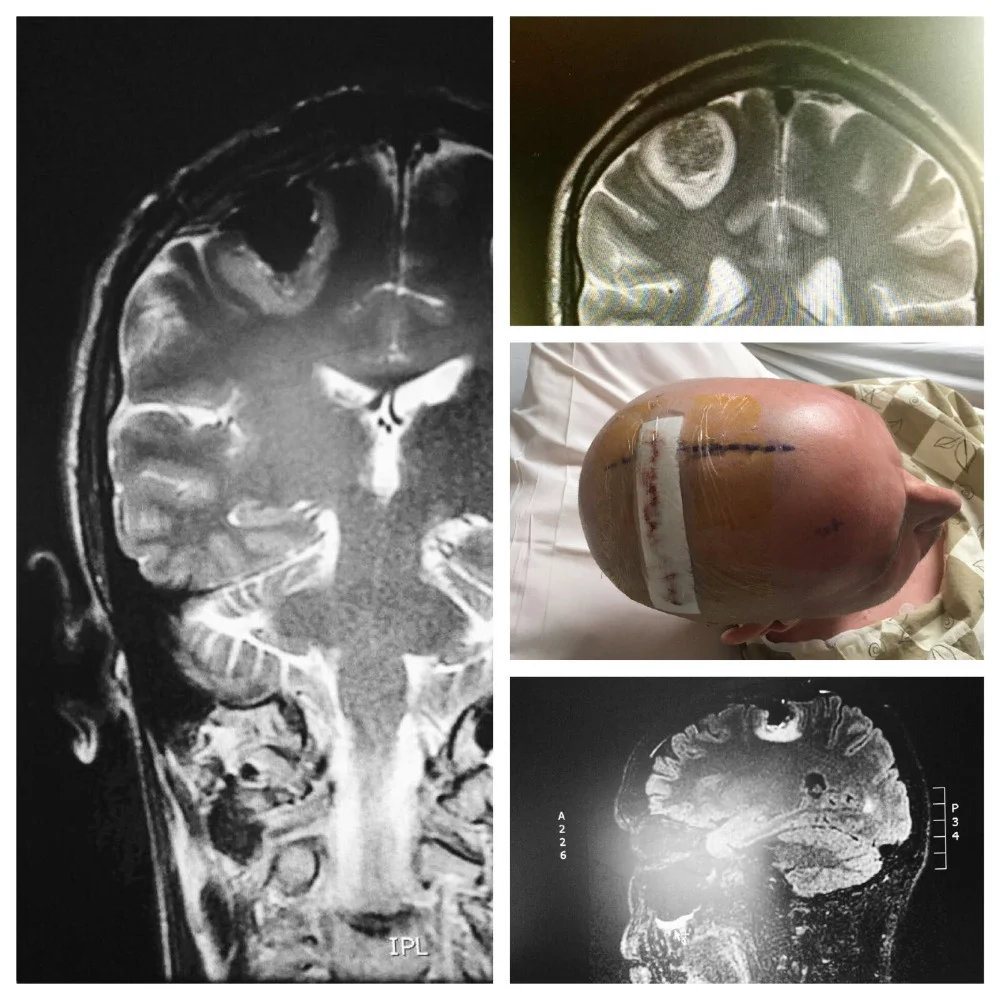

The following day, yesterday morning, while driving back from an appointment, I lost complete mobility in my left arm. unsure if this was a seizure, a stroke... a clotting issue, my sister took me to the ER. as most of my ER stories go, they did a number of tests, the first of which, after vitals, was a CT scan of the head. what they discovered explained the loss of mobility/motor function in my left arm -- a 3.2cm lesion located on the back rear (right) lobe in and around parietal and occipital lobe. (this is what im piecing together from the various doctors I've met. still trying to grasp the facts.) the MRI i had on jan 30 showed no sign of this (what is assumed to be) metastatic spread.

Unlike the other brain lesion that was dealt with using solely stereotactic radiosurgey (SRS) in early October (2016), this one will initially be surgically resection and then SRS will be used. the main reason for that is its size.

when i first met the neurosurgeon he was optimistic that the 3.2cm lesion in my brain was merely causing swelling and this swelling was pressing against a supplementary motor cortex (voluntary movement HQ). he was optimistic. however, his tone changed after steroids, administered to help decrease swelling when the lesion was discovered, didn’t assist in bringing back the slightest movement in my fingers or arm. i am able to hoist the weight of the arm using my shoulder, but there is no grip or dexterity in my fingers, hand, wrist, etc. & bending it at the elbow isn’t yet possible entirely on my own/without extra guidance from my right arm. it is the strangest thing to be looking at my fingers and telling them, asking them, pleading with them to move and they don’t.

rather than just being swelling from the lesion causing pressure, the surgeon feels part of the lesion (part of it) was pushing against one of the primary motor cortex bands that run along this particular section of the brain. i am still trying to wrap my head around this… but it does explain the continued immobility of the extremity.